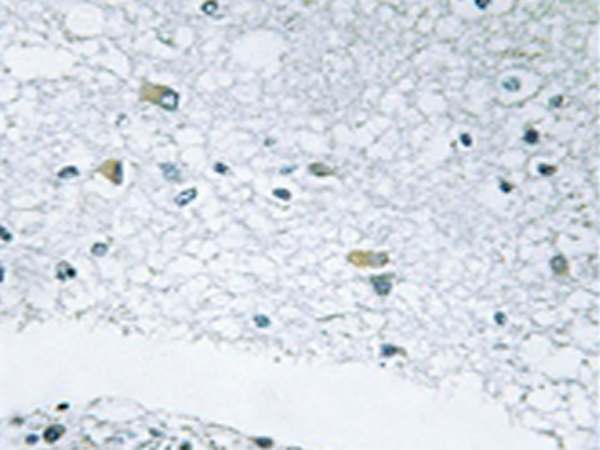

IHC positive control:

Human brain tissue

IHC Recommend dilution:

50-100